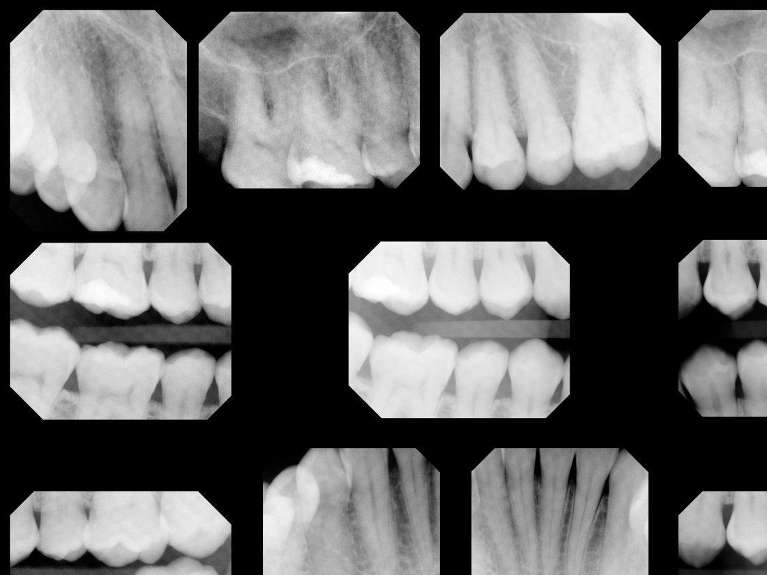

Digital X-Rays

Modern digital dental x-rays benefit patients in a number of ways:

- Digital x-rays expose patients to considerably less radiation than conventional film x-rays.

- Digital x-rays require almost no time for development, reducing time spent waiting in the dental chair.

- Digital x-rays allow for incredibly precise and accurate images for timely diagnoses.

- Digital x-rays are securely stored in your digital file and can be securely sent to your insurance company or specialists, when necessary.

Because no chemicals are needed for developing and no space is needed for film storage, digital x-rays are better for the environment.